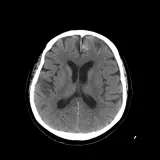

Over 2,100 interactive radiology cases, curated by radiologists for your level of training. Scroll, window, and view cases full screen — just like on PACS. Click linked findings in each writeup to jump straight to them on the image. Cases include sample reports, a focused discussion section, original illustrations, and videos.

Des cas entièrement interactifs avec les outils attendus d'un PACS — défilement, fenêtrage, zoom, déplacement, mesures, ROI et mode plein écran.

Des annotations détaillées mettent en évidence les résultats clés directement sur les cas. Cliquez sur les résultats liés dans les descriptions de cas pour accéder à leur emplacement exact sur l'examen.